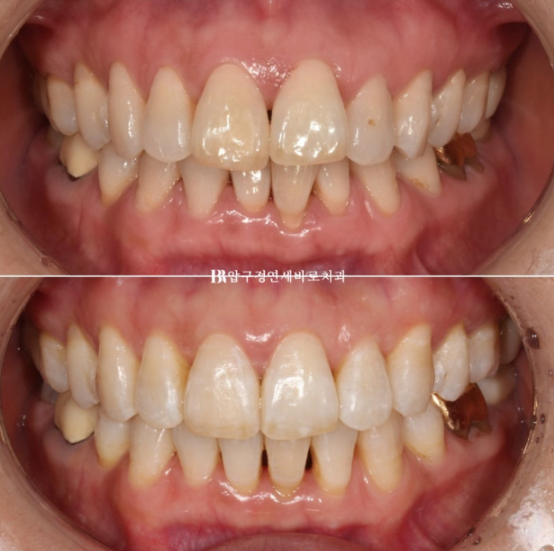

위 앞니 두개가 튀어나와있고 회전이 되어있습니다.

정식용어는 아니지만 이것을 나비치아 라고 부릅니다.

이 정도면 인비절라인 라이트로도 충분히 교정이 가능합니다.

배열이 가지런해졌고 소량의 치간삭제를 통해 블랙트라이앵글도 줄었습니다.

단 위 앞니 높낮이 단차가 있어서 이 부분을 추가장치에서 해결하기로 했습니다.

이 정도도 충분히 좋지만 100점 목표를 위해 추가장치 제작을 합니다.

추가장치를 2월부터 5월까지 3달간 10일씩 꼈고 마무리 했습니다.

24.05

위 앞니 블랙트라이앵글은 치간삭제를 통해 줄었으나 삐뚤했던 아래 앞니가 가지런해지면서 블랙트라이앵글이 생겼습니다. 아래도 마찬가지로 치간삭제를 통해 블랙트라이앵글 사이즈를 줄였지만 치간삭제는 치아에 무리가지 않는 선에서 하는 것이 좋습니다.

걱정하시는 교합도 좋습니다.